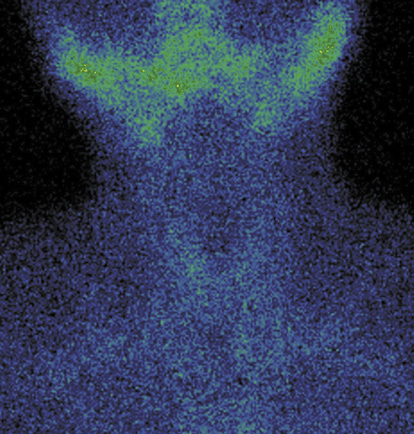

7. Fig. 7. Graves' disease (diffuse-heterogeneously increased radiopharmaceutical uptake in both thyroid lobes with a pyramidal lobule). | |